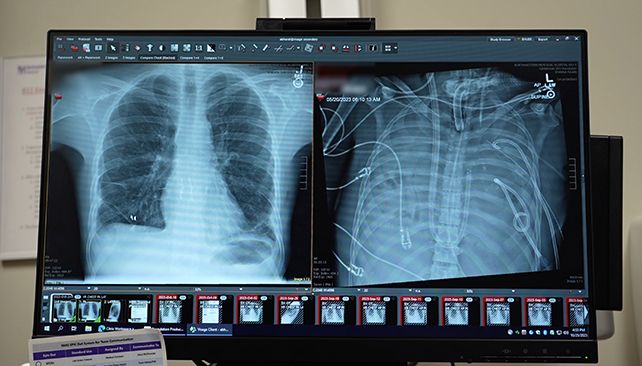

รายงานระบุว่าผู้ป่วยชายวัย 33 ปี ซึ่งเผชิญภาวะการหายใจล้มเหลวเฉียบพลัน (ARDS) ได้เข้ารักษาตัวที่โรงพยาบาลนอร์ธเวสต์เทิร์น เมโมเรียลในสหรัฐฯ เมื่อฤดูใบไม้ผลิปี 2023 โดยอาการของเขาย่ำแย่ลงจนกลายเป็นโรคปอดอักเสบเนื้อตายและภาวะติดเชื้อในกระแสเลือดขั้นรุนแรง แม้ใช้เครื่องช่วยหายใจแต่อาการยังคงไม่ดีขึ้นจนกระทั่งเกิดปัญหาไตวายและหัวใจหยุดเต้น ทีมแพทย์นำโดย ดร.อันกิต ภารัต ศัลยแพทย์ทรวงอกประจำคณะแพทยศาสตร์ไฟน์เบิร์กของมหาวิทยาลัยนอร์ธเวสต์เทิร์นในเมืองชิคาโก จึงตัดสินใจใช้ระบบปอดเทียมรุ่นพัฒนาใหม่มาพยุงชีพของผู้ป่วยหลังจากผ่าตัดเอาปอดที่ติดเชื้อออกมา โดยอาการของผู้ป่วยเริ่มดีขึ้นภายในเวลา 48 ชั่วโมง ไตและหัวใจกลับมาทำงานตามปกติจนไม่ต้องฉีดยากระตุ้นความดันเลือด ต่อจากนั้นผู้ป่วยได้รับการผ่าตัดปลูกถ่ายปอดสองข้างและไม่มีสัญญาณร่างกายต่อต้านอวัยวะหรือความผิดปกติใด ๆ ของปอด